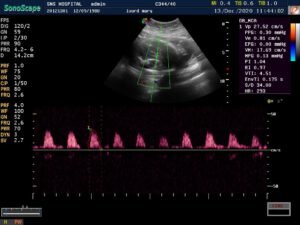

The insulin requirement kept changing as the pregnancy advanced .she was already on aspirin and her uterine Doppler showed low resistance flow. Growth scan with Doppler every 4weeks done from 20 weeks.

There was growth lag of 2weeks @ 27 weeks gestation, Doppler U/A 50th percentile followed by growth scan every 2weeks with Doppler.

The parameters fell below 50th percentile but the interval growth was satisfactory.